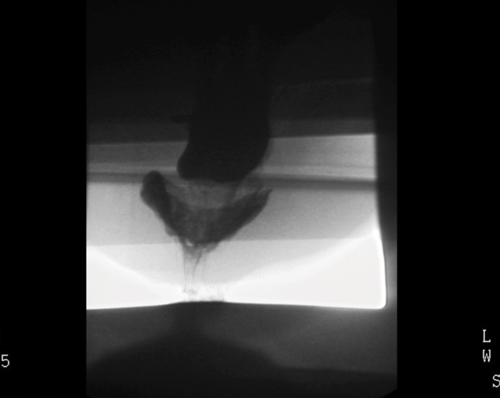

To achieve opacification of small bowel loops in fluoroscopic proctography, approximately 300ml of oral barium suspension is given 45 minutes prior to the beginning of the procedure. This is useful for the diagnosis of possible enterocoele (loops of small bowel in the pelvis). An initial digital rectal examination is performed with the patient in left lateral decubitus position in order to assess the tone of the sphincter complex and to confirm the safety of inserting a rectal tube. Approximately 200-300ml of thick barium paste is injected into the rectum via the tube. The entire examination is recorded through videofluoroscopy. Several video recorded images are obtained in left lateral and in supine positions with the patient responding to requests of ‘squeeze up’, ‘bear down’ and ‘cough’. This is to evaluate the response to increased intra-abdominal pressure. Subsequently, the patient is asked to sit on a specially designed chair and is instructed to empty the rectum completely. This part of the procedure is also video recorded and additionally spot images taken. The whole examination lasts approximately 10-15 minutes. Evaluation of the posterior compartment (rectum) with assessment pelvic floor descent is assisted by using an imaginary line drawn in the lateral views from the pubic bone anteriorly to a fixed segment of coccyx posteriorly (Figure 1).

Figure 1c: Intussusception on fluoro proctogram.